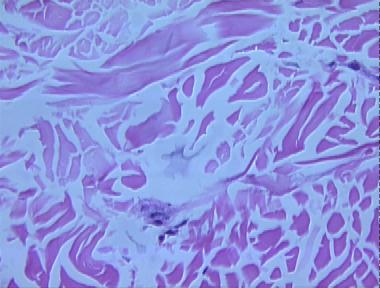

scleredema

Histologic Features